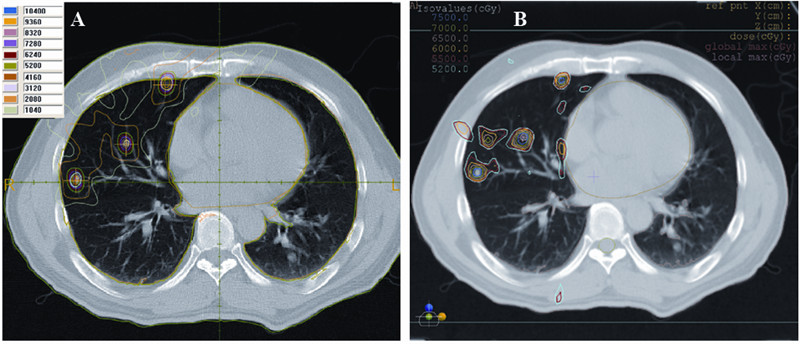

不论采用仰卧体位还是俯卧体位,γ刀治疗都 能很好的保护患者的肺、心脏和脊髓,见图 1~4、表 1。

处方总剂量为52 Gy时,90%的GTV靶区得到 相当于常规放疗94 Gy剂量的照射,仰卧体位双 肺的平均剂量为8.36 Gy,V20、V10和V5分别为 12.60%、24.60%和37.40%,俯卧体位双肺的平均 剂量为8.15 Gy,V20、V10和V5分别为12.67%、 25.10%和40.40%。10 Gy和20 Gy等剂量线范围比 较局限,高剂量区只集中在靶区周围,即使靶区 之间距离较近,靶区外也未出现剂量热点(剂量 大于处方剂量,且大于1.5 cm的区域)。仰卧体位 心脏所受剂量也非常低,俯卧体位即使靶区很靠 近脊髓,脊髓的剂量也比较低。

![]() | 图 1 仰卧病例伽玛刀和3DCRT治疗计划剂量分布比较 Figure 1 Comparison of dose distributions for a supine case between γrays radiotherapy and 3DCRT A:γrays radiotherapy;B:3 dimensional radiotherapy(3DCRT) |

由图 1、2可以看出,在治疗肺多发转移灶病例 中,γ刀剂量聚焦的优势在治疗相互之间距离很近 的几个小病灶中得到很好的体现。3DCRT计划中, 所有病例中最少使用了26个射野,最多使用了29 个射野。在病灶彼此比较靠近的区域,3DCRT由于 射野相互交叉,不可避免出现热点(平均有7个热 点),而γ刀的高剂量区只分布在靶区周围,避免了 靶区外热点的形成。仰卧和俯卧病例3DCRT全肺平 均剂量和V20分别为16.57 Gy、24.2%和17.13 Gy、 25.3%,均远高于γ刀的剂量学数据,见图 1、2。 3 讨论